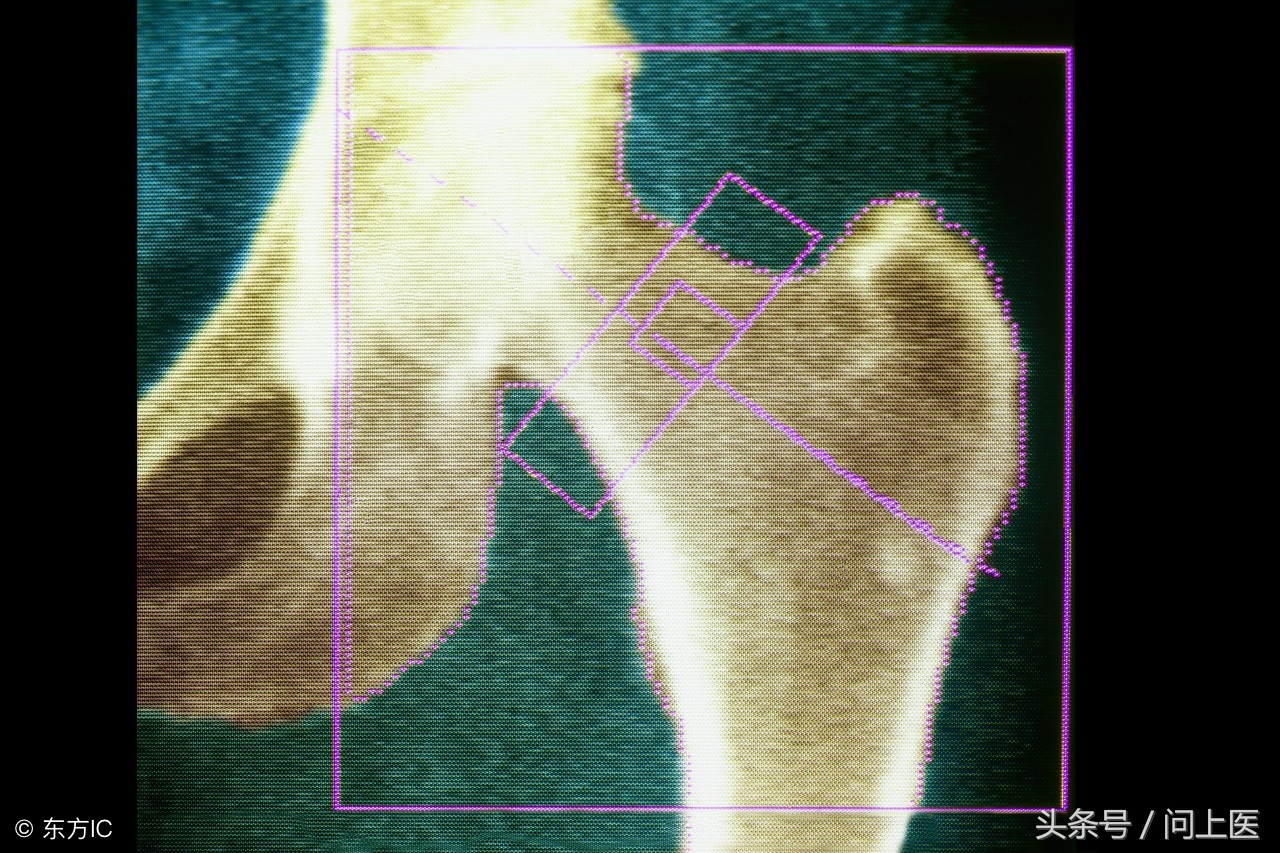

1.双能X线吸收法(DXA)

这是测量骨密度最准确的方法。测试中,需要使用两束不同的X射线来估测人体脊柱和髋骨的骨密度。强壮、质密的骨骼能够通过的X射线更少,测试中会比较两束X射线被骨骼和软组织挡住的量。DXA可以测量出低至2%的年骨质损失量,并且测量快速使用的辐射剂量比较低。而单能X线吸收测定法(SXA)可用于测量脚跟和前臂的骨密度,但SXA的使用次数不像DXA那么高。